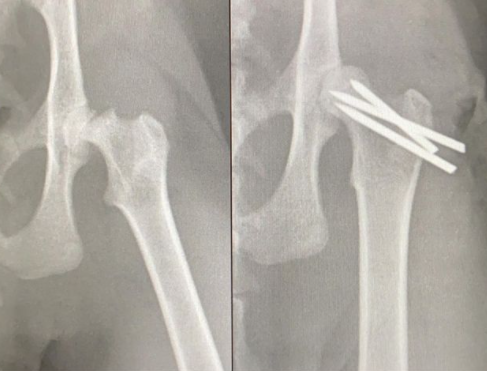

La traumatología veterinaria es una rama que requiere una gran especialización para poder dar soluciones efectivas a las lesiones que presenten nuestras mascotas. Esta especialidad veterinaria abarca el tratamiento de las lesiones que afectan al aparato locomotor de los animales.

Actualmente, esta especialidad se extiende más allá del tratamiento de las lesiones de origen traumático, ocupándose también de las afecciones congénitas o adquiridas de forma preventiva, terapéutica y rehabilitadora. Por ello, no hablamos solamente de traumatología, sino también de ortopedia.

En Vetland contamos con algunos de los mejores profesionales especializados en la materia del país, con los que somos capaces de dar solución a los casos más complejos. Además, aplicamos nuestros conocimientos en técnicas mínimamente invasivas para conseguir los mejores resultados a la vez que minimizamos los riesgos asociados a la intervención y el tiempo de recuperación postoperatoria.